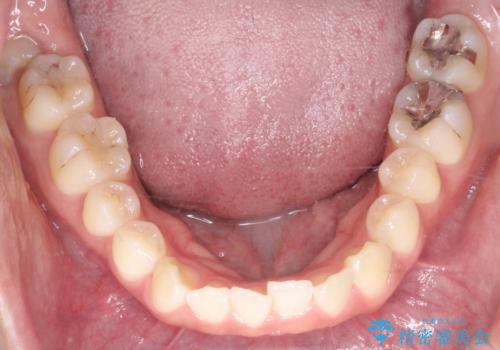

- 治療計画

治療では、審美ワイヤーを使用し、目立ちにくく配慮しながら矯正を進めました。上顎にリンガルアーチと矯正用アンカースクリューを用いて臼歯部を安定的に遠心移動させ、歯列全体のスペースを確保しました。その後、回転していた前歯を正しい位置に配列し、全体的な歯並びの改善を行いました。治療中は、装置の適切な管理と口腔衛生を徹底することが重要でした。結果として、見た目だけでなく機能的にも優れた歯列を実現することができ、患者様にもご満足いただけました。